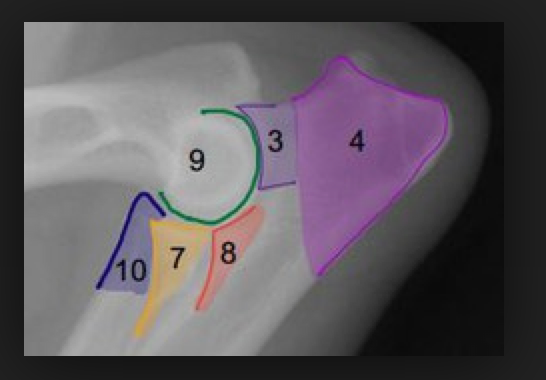

WHAT VIEWS ARE THESE?

Normal canine elbow

WHICH PROJECTIONS ARE THESE?

Assess positioning:

•

Mediolateral projection

avoid rotation of the humeral condyle

note the humeral trochlea (medial portion) articulates more distally than the capitulum (lateral portion)

Craniocaudal projections

On a well-positioned craniocaudal projection (in this case, of the left elbow), the olecranon of the ulna is

positioned on midline, bisecting the humeral metaphysis and epiphysis.

On a cranio-10°-lateral-caudomedial oblique view (in this case, of the right elbow), the olecranon is

superimposed over the lateral aspect of the distal humerus. This view is sometimes used to free-project the

medial coronoid process.

In addition a ‘neutral’ position mediolateral view may be taken, and is useful for evaluation of the elbow joint congruity.

With this view however, the anconeal process is obscured by the medial epicondyle of the humerus.

Evaluate:

On the mediolateral projection:

The width of the joint space between the humerus and radius, as well as the humerus and ulna

The congruency of the ulna notch and the humeral condyle

The anconeal process for osteophyte formation, and union with the olecranon tuber

The base of the medial coronoid process for sclerosis

On the craniocaudal projections:

The cranial and medial border of the medial coronoid process for osteophytes or fragmentation

The contour of the joint surface of the humerus, for osteochondrosis lesions and sclerosis

The radial head and humeral epicondyles for osteophyte formation

The humeral epicondyles for enthesiophyte formation

Flexed medio-lateral (ML), craniocaudal (CrCd), and Cr10LCdM oblique projections are provided.